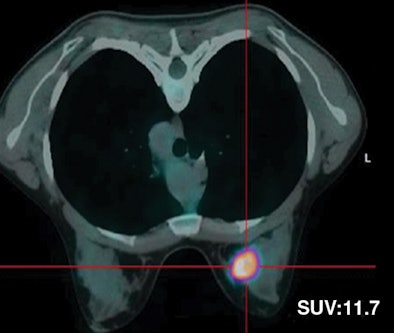

| Fifty-five-year-old woman with ductal infiltrating adenocarcinoma measuring 15 mm in maximum transverse diameter. Axial fused PET/CT images obtained with patient in prone position at time point 1 (above) and time point 2 (below) show corresponding standard uptake values. All images courtesy of the American Roentgen Ray Society. |

| Thirty-two-year-old woman with ductal infiltrating adenocarcinoma measuring 18 mm in maximum transverse diameter. Axial fused PET/CT images obtained with patient in prone position at time point 1 (above) and time point 2 (below) show corresponding standard uptake values. |